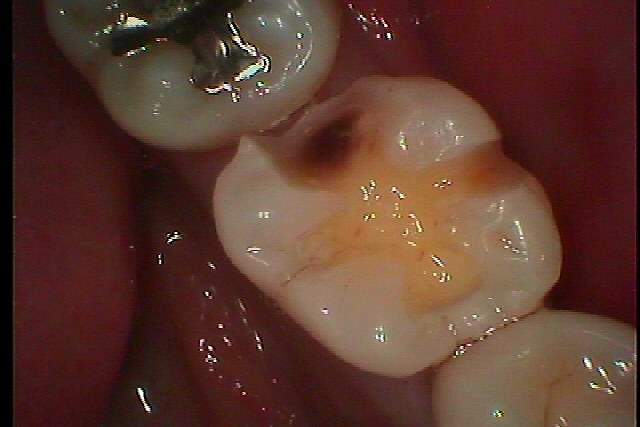

左下の奥歯が物が挟まりやすくなった 診てほしい 虫歯治療の実際|お知らせ |広島市安佐南区の歯科医院 左下の奥歯が物が挟まりやすくなった 診てほしい 虫歯治療の実際 トップ お知らせ・ブログ お知らせ 左下の奥歯が物が挟まりやすくなった 診てほしい 虫歯治療の実際 左下の奥歯が物が挟まりやすくなった 診てほしい 虫歯治療の実際 銀歯を外していきます 遠心部に穴が開いています デンタルレントゲンでもこのようにわかります 穴はごく一部に見えても虫歯は中深くまで大きく進行しています ここまで虫歯が存在しています CR樹脂にて覆罩を行い型取りを行っていきます セレックプライムスキャンにてセラミックを作成して このようにきれいに仕上がりました Web診療予約 初めての方へ 選ばれ続ける理由 院内設備について 歯が痛いしみる一般歯科 歯がぐらぐらする歯周病 健康な歯を保ちたい予防歯科 子供の虫歯予防をしたい小児歯科 銀歯をセラミックに審美歯科 白い歯を目指しませんか?ホワイトニング 矯正専門医がいるので安心矯正歯科 抜けた歯を補いたいインプラント・入れ歯 医院案内 スタッフ紹介 メリィハウス歯科クリニックオフィシャルホームページ ラベンダー歯科クリニックオフィシャルホームページ お知らせ・ブログ ホーム 診療科目 一般歯科 歯周病治療 予防治療 小児歯科 審美治療 ホワイトニング 矯正歯科 入れ歯・インプラント マウスピース矯正 初めての方へ 院長・スタッフ 設備紹介 医院案内・アクセス メニューを閉じる